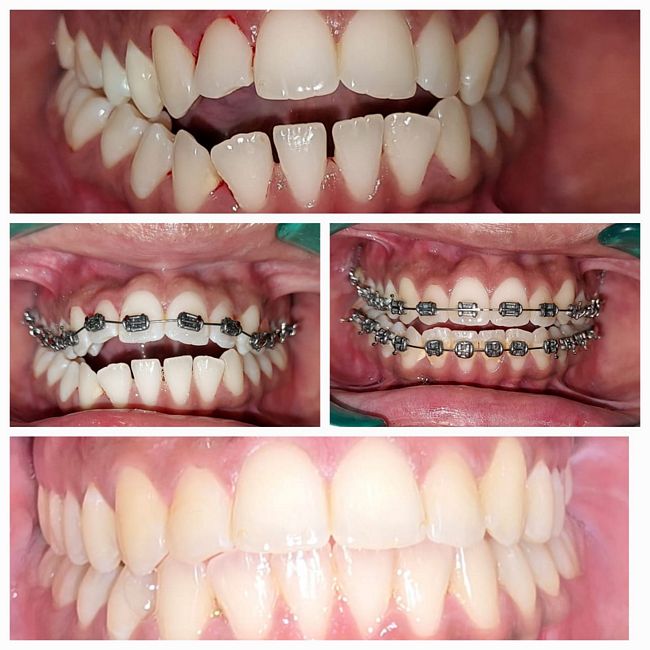

Dr. Jaipal Reddy is an experienced and highly regarded dental surgeon and cosmetic dentist based in Koramangala, Bengaluru. He is the founder and lead dentist at JP Dental Clinic, a well-established dental practice known for comprehensive, patient-centric oral care. Dr. Reddy holds a Bachelor of Dental Surgery (BDS) degree from the Government Dental College and Research Institute, Bangalore, and brings over 25 years of clinical experience in general dentistry, endodontics, and cosmetic dental procedures.